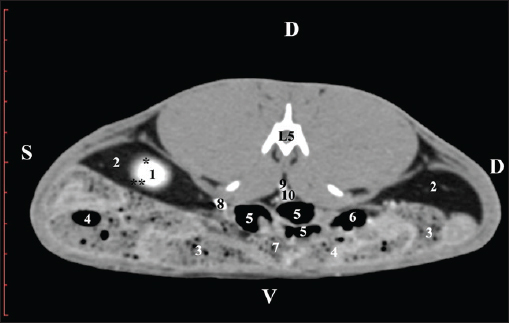

Fig. 11. Pre-contrast computed tomography (CT) anatomical scan of the regio-abdominis media at the caudal L4 edge level. (1) Ren sinister; (2) pelvis renalis; (3) ureter; (4) adipose collections; (5) cecum; (6) colon ascendens; (7) colon transversum; (8) colon descendens; (9) mesenterium; (white arrows) recessus renalis; (*) crista renalis. The L5 scan revealed the caudal end of the left kidney. It was adjacent to some small intestinal segments, including the duodenal pars ascendens, ileum, cecum, and colon ascendens (Figs. 12 and 13).

Fig. 12. Pre-contrast computed tomography (CT) anatomical scan of the regio-abdominis media at the cranial L5 edge level. (1) Ren sinister; (2) adipose collections; (3) cecum; (4) colon ascendens; (5) jejunum; (6) pars ascendens of the duodenum; (7) colon transversum; (8) colon descendens.

Fig. 13. Pre-contrast computed tomography (CT) anatomical scan of the regio-abdominis media at the caudal L5 edge level. (1) Ren sinister; (2) adipose collections; (3) cecum; (4) colon ascendens; (5) colon transversum; (6) colon descendens. Post-contrast CT imagingCT anatomical study at the Th13 level was used to define the right kidney zones. The medulla renalis was found as a hyperattenuated soft tissue with peripheral linear and wavy margins that reached the relatively hypoattenuated renal cortex. The most peripheral structure was the capsula adiposa, characterized by hyperattenuated soft tissue and uniform relief. The hyperattenuated aorta abdominalis, v. cava caudalis, and a. renalis appeared medially to the right kidney (Fig. 14).